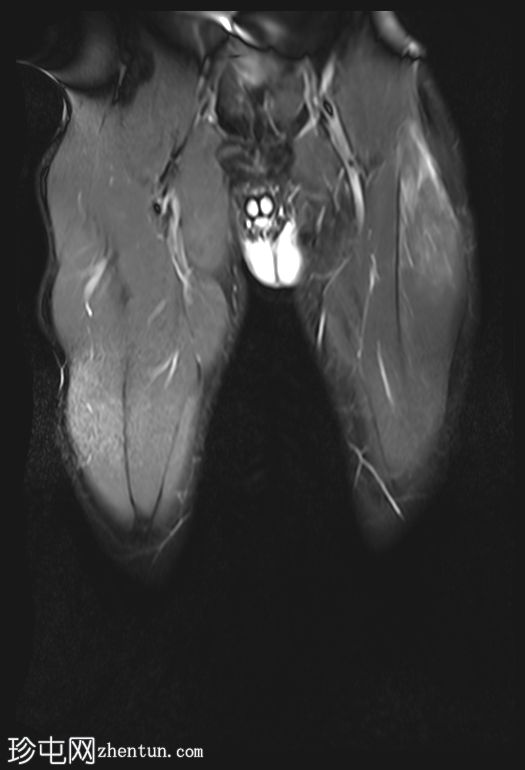

冠状位

T1加权像

股直肌近端和中段前外侧可见一水肿性高信号影,长约15厘米,宽约3厘米。肌纤维轻度分离,但未见撕裂。肌内未见积液;在相邻肌间隙可见一条细小的液线环绕肌肉,延伸至近端肌腱交界处。

股直肌中段的间接肌腱轻度增厚,伴有肌腱周围水肿,提示2B级拉伤。但肌腱保持连续性,骨性附着良好,未见撕裂。